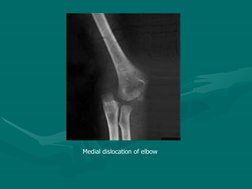

Diagonosis is often confirmed on X-rays

X-RAYS

Posterior dislocation of elbow

Medial dislocation of elbow

Divergent dislocation of elbow